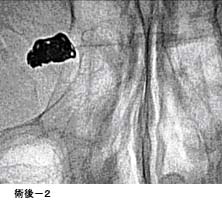

頸動脈狭窄症に対するステント留置術

(現在、ステントは保険適応となっておりません。)